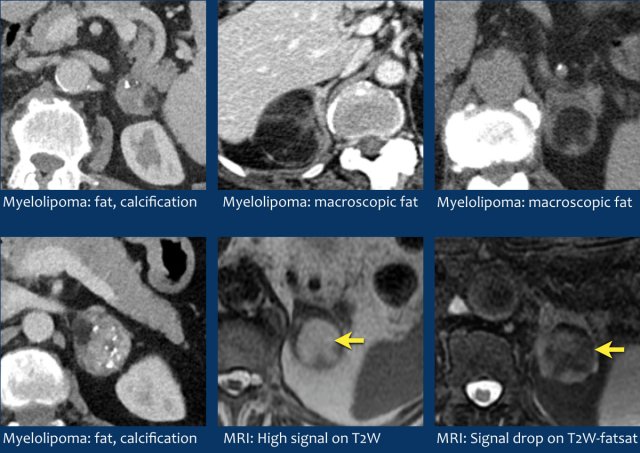

Myelolipoma

Myelolipomas are benign tumors composed of bone marrow elements.

Usually they are easy to recognize on CT or MR because they contain areas of macroscopic fat.

Calcifications are seen in 24% of cases.

The adrenal mass seen here on CT contains macroscopic fat, which is specific for the diagnosis myelolipoma.

On the right a different case with high SI on T1W-image indicating macroscopic fat in a myelolipoma.

CT image of another adrenal mass mainly composed of macroscopic fat.

Diagnosis: myelolipoma.

Myelolipomas Myelolipomas

Myelolipomas

Adrenal myelolipomas are benign, relatively rare (0,08-0,2%) tumors that contain variable amounts of bone marrow elements and mature fat.

Myelolipomas are usually asymptomatic, unless they are very large (due to mass effect) or bleed [5].

The presence of macroscopic fat makes them easy to recognize on CT or MRI.

Attenuation on nonenhanced CT will be well below 0 HU.

At MR imaging the fatty portions will be hyperintense on non fat-saturated T1-weighted images and show signal dropout on fat-saturated T1 or T2-weighted images.

Calcifications are seen in approximately 24% of cases.